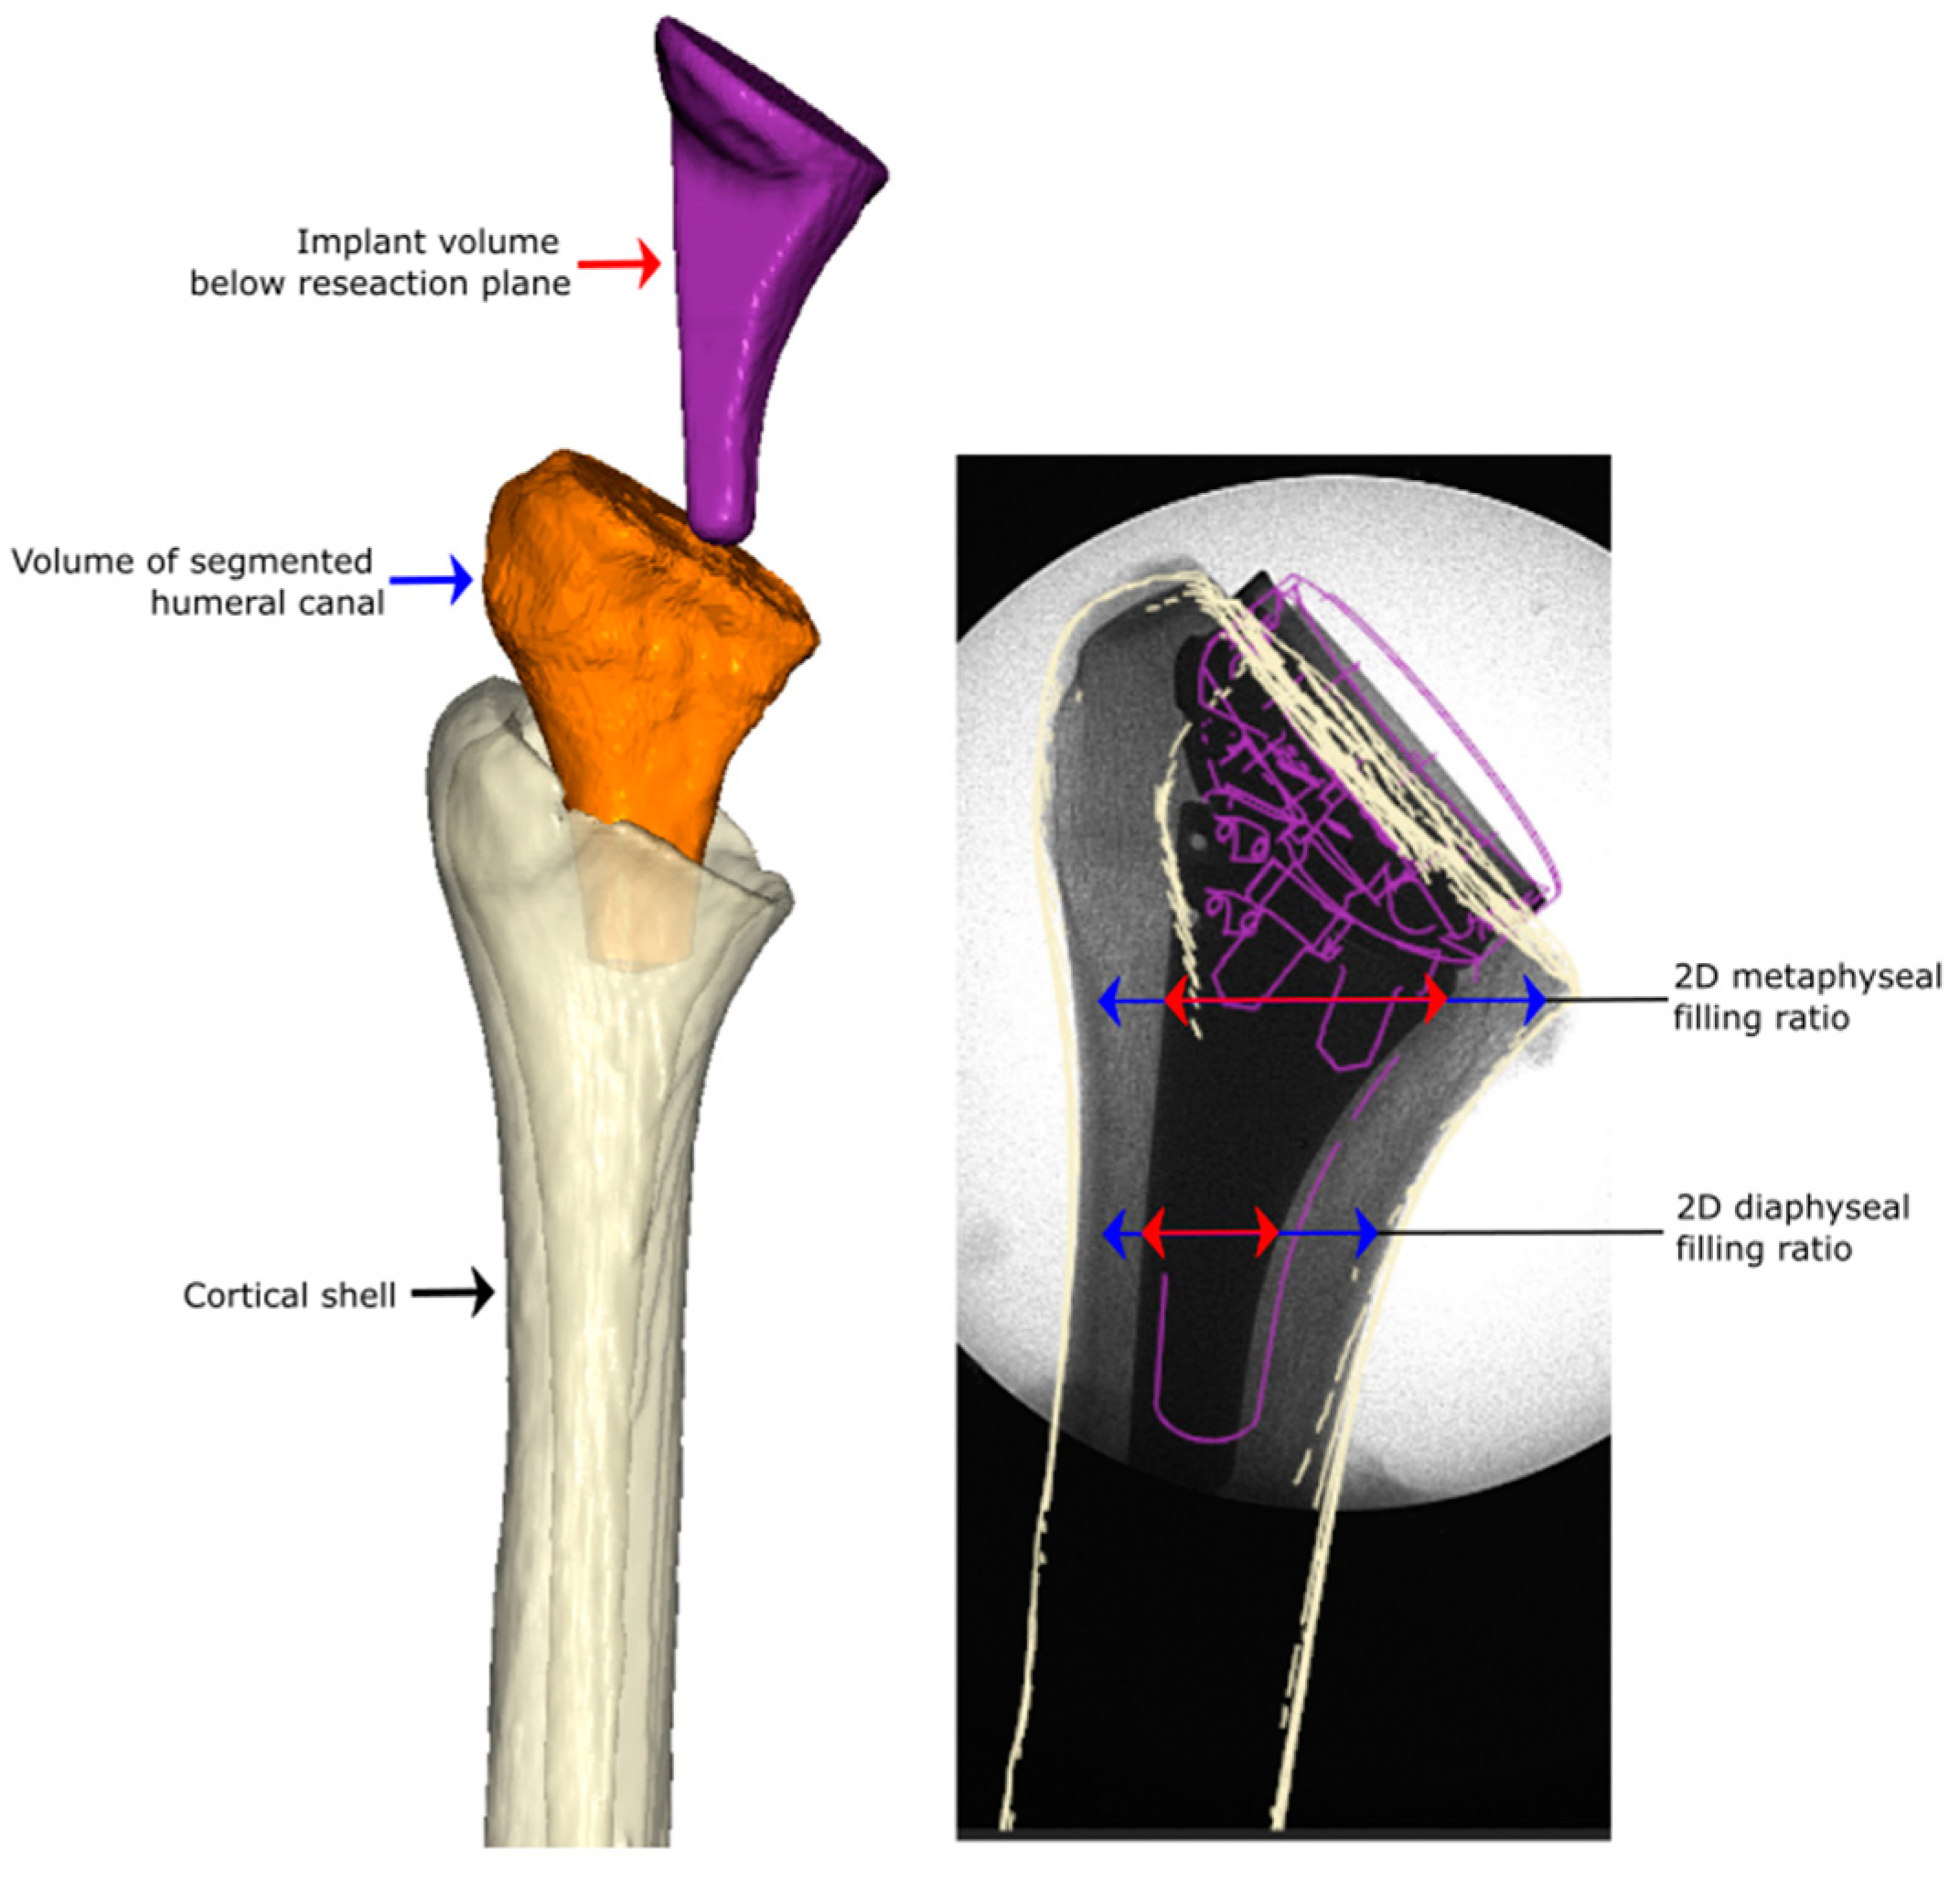

2.2. Pre- and Postoperative Canal Fill Analysis